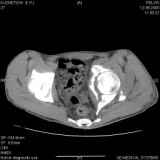

Уважаемые коллеги! Хотелось бы услышать совет по тактике лечения представлленого больного.Поступил после лечения в одном изотделений области. Травма 2,5 месяца назад. После выведенияиз шока был произведен остеосинтез перелома бедра, предплечья, до перевода к нам проводилосьвытяжение по оси шейки бедра за стержень, введенный в большой вертел. На сегодня деформацияригидна, клинически мобильности не определяется. Заранее признателен. P.S. Данный вид травм не включен в перечень "высокотехнологичных операций", направить длялечения по квотам Минздрава очень сложно.

Все-таки надо бы начать не с КТ, а с обзорного снимка таза и косых проекций впадины.

Это обзорные и косые снимки

Привет, Леонид. Оскольчатый высокий двухколонный перелом в такие сроки трогать не надо, т.к. это про такие переломы сказано: "кто с ножом на Ж. пойдет тот в ней и останется...".